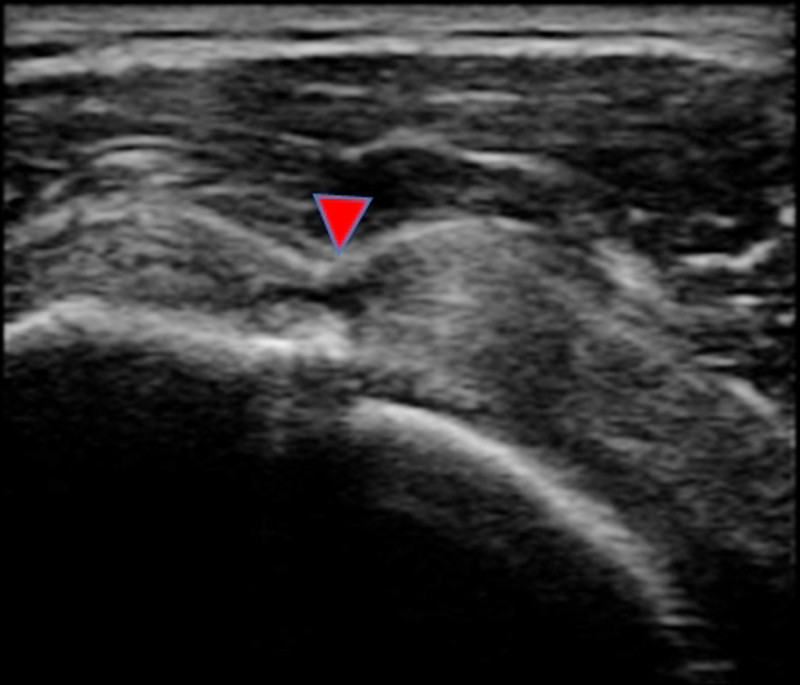

我在診間幫陳小姐掃軟組織超音波,發現她的右肩旋轉肌肌腱嚴重撕裂(圖1),所以造成疼痛,以及手舉不高等現象。

診斷肩膀旋轉肌肌腱撕裂,除了詢問病史以及理學檢查外,最重要的診斷工具是軟組織超音波。X光是大家最熟悉的檢查,但除了骨折、脫臼等跟骨頭較相關的問題外,像肌肉、肌腱、韌帶等軟組織的問題,光憑X光並無法診斷出來。